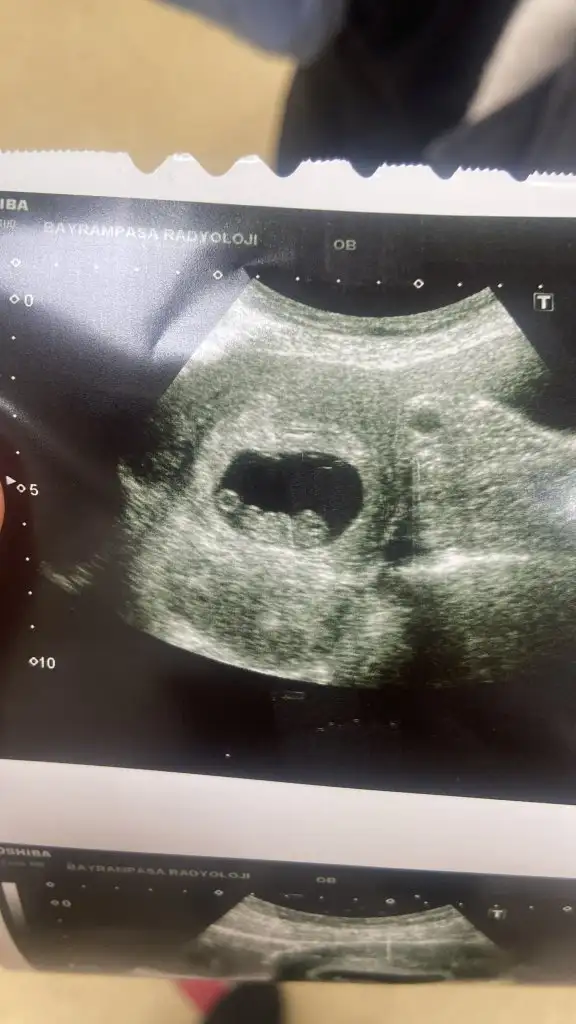

Canım vajinadan bakıldıysa aslında bebeğin konumu sağda demek… ama dediğim gibi bebeğin konumu değil de plasentanın konumu burda önemli olan .Nasıl anladınız :) bu arada vajinadan bakıldı benim

Ultrason resminizi paylaşabilir misiniz? Bu arada arkadaşın aslında vajinadan bakılmış, yani bebek sağda aslında.Benim bebeğim erkek olacak. Benim kesem ve duruşuyla birebir aynı

Evet canım benim vajinadan bakıldıCanım vajinadan bakıldıysa aslında bebeğin konumu sağda demek… ama dediğim gibi bebeğin konumu değil de plasentanın konumu burda önemli olan .

Şimdi sağdaysa kız demekmiş ama dediğim gibi asıl önemli olan plasentası. Yabancı kaynaklarda araştırdım biraz. Bebeğin sağ veya solda olmasıyla yapılmıyormuş tahmin… o yüzden işte doğum yapmış hanımlardan rica etmiştim resimleriEvet canım benim vajinadan bakıldı

Canım bebeğin konumu değil plasentanın konumunu sorarsan daha iyi olur. Bir de 7-8 haftalık ultrason resmî varsa paylaşır mısınız lütfen?kese fasülye şeklindeyse erkek demişlerdi kız bebeğim konumunu bilmiyorum karnımın ortasından bakıyor hep ultrason için ama gidince sorarım sağda mı solda mı diye

Canım bebeğin konumu değil plasentanın konumunu sorarsan daha iyi olur. Bir de 7-8 haftalık ultrason resmî varsa paylaşır mısınız lütfen?

Bak canım resim ekledim. İlk resimde vajinal bakılmış. Bebek sağ da plasentası solda yani bu aslında bebek solda plasenta da sağ da demek. Yani bu kız bebek diye teyit edilmiş. İkinci resim karından bakılmış yani olduğu gibi bebek solda ve plasentası da solda bu bebek erkek diye teyit edilmiş. O yüzden diyorum ki bebeğin konumu değil, plasentanın konumu lazım bize.evet kimse yaZmıyor ben yeni konu açayım mı sende oraya gel belki görüntü atan olur karşılaştırırız birde ben anlamıyorum görüntülerden nasıl anlıyorlar

Benim de vajinadan sağda görünüyor ya o zaman kız mı olur dersinBak canım resim ekledim. İlk resimde vajinal bakılmış. Bebek sağ da plasentası solda yani bu aslında bebek solda plasenta da sağ da demek. Yani bu kız bebek diye teyit edilmiş. İkinci resim karından bakılmış yani olduğu gibi bebek solda ve plasentası da solda bu bebek erkek diye teyit edilmiş. O yüzden diyorum ki bebeğin konumu değil, plasentanın konumu lazım bize.

Bak resim vajinadan yapıldığı için aslında bebek solda demek oluyor ama vajinadan sağ da görünmüş. Yani genelde bebek sağdaysa kız diyorlar ama bu doğru değil, plasentası sağdaysa kız. Bunu da biz pek anlayamıyoruz ama parlak bir alan oluyor ona dikkat etmek lazım. O sağdaysa kızmış yani…Benim de vajinadan sağda görünüyor ya o zaman kız mı olur dersin![]()

Senin bebeğin evet aslında sağdaymış ama plasentası nerde? İşte onu bilmek lazım. O da sağdaysa kız demekmiş.Benim de vajinadan sağda görünüyor ya o zaman kız mı olur dersin![]()